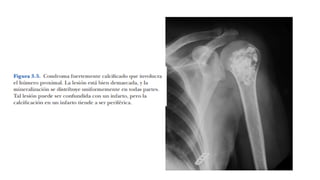

•En huesos largos, su calcificación es similar a un infarto óseo intramedular

• Infartos de hueso tienden a tener margen esclerótico bien circunscrito